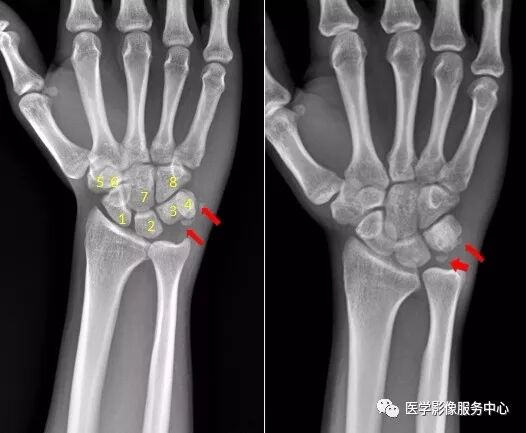

图片

1.舟骨   2.月骨   3.三角骨   4.豌豆骨   5.大多角骨   6.小多角骨   7.头状骨   8.钩骨

右腕关节近三角骨、豆状骨内侧见多个游离骨碎片影,小碎骨片分离移位。考虑为,右腕关节三角骨,豌豆骨粉碎性骨折。

右侧桡骨远端可见不规则透亮骨折线,并累及关节面。右侧桡骨远端骨折

尺骨茎突见游离骨碎片影。右侧尺骨茎突骨折。